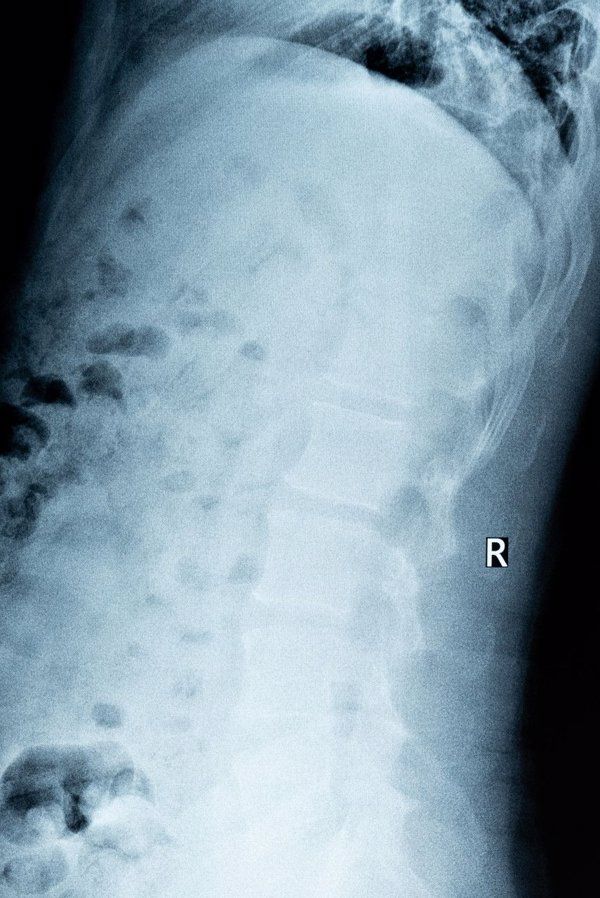

骨质增生是一种慢性疾病,需要综合治疗方法。虽然竹针无法消除骨赘,但其可促进局部血液循环,放松紧张肌肉,从而减轻因骨质增生引起的疼痛等症状。为确保安全有效,建议寻求中医师指导使用竹针,并结合其他非药物疗法如物理治疗等。

在中老年人群中,骨质增生较为常见,尤以颈椎病、腰椎病多见。日常生活中应避免长时间保持一个姿势不动,以免加重不适症状。